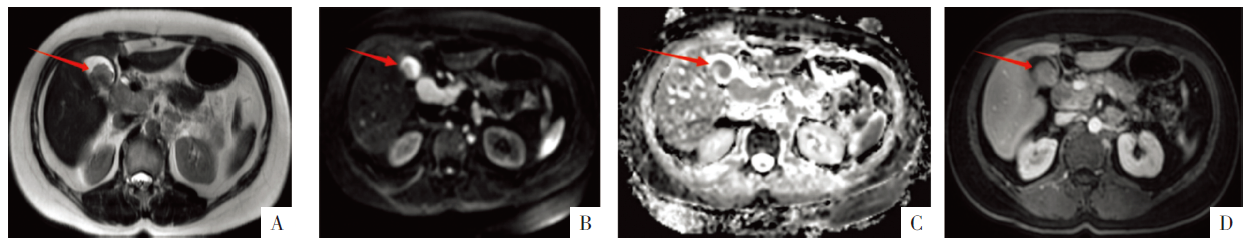

• 图3 胆囊病变的MRI影像。A—C图分别为T2WI、DWI、ADC图,D图为增强MRI静脉期影像。箭头示胆囊病灶。